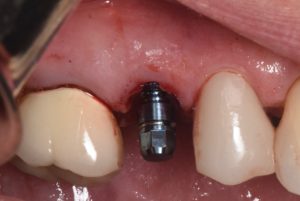

This video demonstrates a fully guided immediate implant placement protocol following premolar extraction, combined with immediate provisional restoration. The case highlights a digitally driven workflow designed to enhance accuracy, efficiency, and prosthetically guided implant positioning.

Step-by-step, the procedure covers atraumatic tooth extraction, guided implant placement using a surgical guide, and chairside fabrication and delivery of an immediate provisional restoration. Clinical considerations for achieving primary stability, soft tissue preservation, and optimal emergence profile are emphasized to support predictable esthetic and functional outcomes.